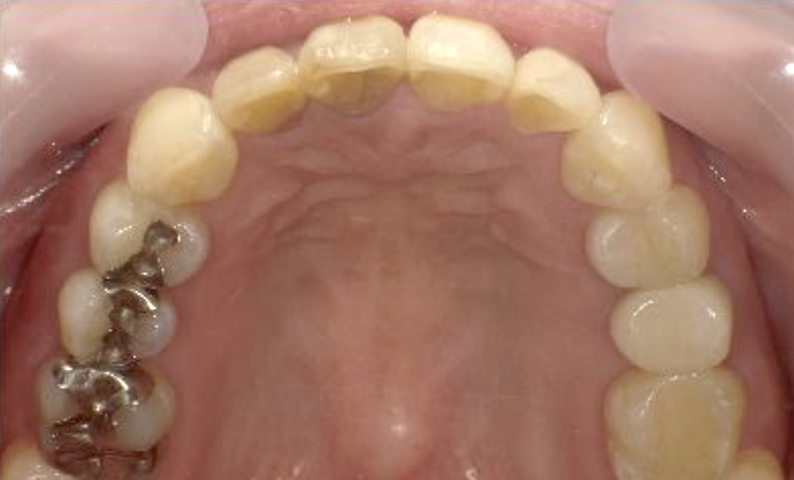

症例_003 下顎だけの部分矯正

治療期間:10ヶ月金額:24万円+税女性前歯のガタガタ下の前歯だけ上顎は補綴治療中

| Before | After |